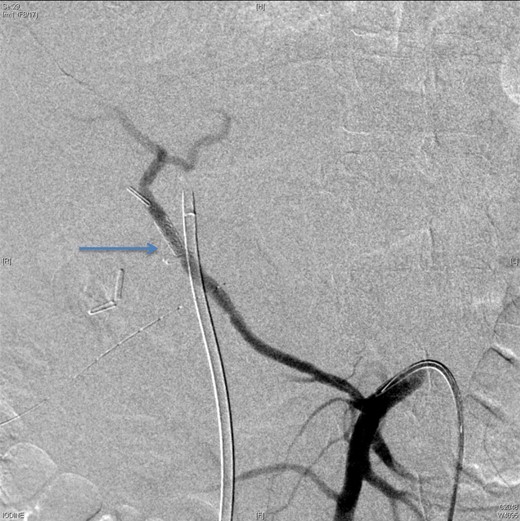

Upon presentation to our center, the patient was febrile (38.9°C) and complained of a left upper limb pain and swelling. The surgical drain was draining a mixture of bile and blood. His WBC count was 14 × 109/l, total bilirubin 35 µmol/l and the direct bilirubin 21 µmol/l. A duplex ultrasound of the upper limb revealed a left brachial vein thrombosis. Hematology was consulted, and a diagnosis of acute upper limb venous thrombosis was established. Owing to the presence of blood in the drain, he was kept on the maximum prophylactic dose of unfractionated heparin. A CT angiography of the abdomen showed two collections, one at the surgical bed near the drain, and the other was subcapsular below the left lateral lobe of the liver, as well as an aneurysm of the replaced right hepatic artery with an active bleeding blush (Fig. 1). The patient was immediately referred for an angiography, which confirmed the CT scan findings (Fig. 2). An arterial stent was inserted at the location of the aneurysm (Fig. 3), and a pigtail drain was inserted to drain any residual collection. An ERCP was also performed, which revealed a Strasberg Class D injury, and a plastic biliary stent was inserted. After the angio-stent insertion and stabilization of the patient, heparin infusion was started. Five days later he developed hematemesis and melena with a significant drop in his Hb to 2 g/l, and his total bilirubin became 183 μmol/l of which 91 μmol/l is direct. A gastroscopy was performed and showed hemobilia (bleeding from the ampulla of Vater). Subsequent angiography demonstrated a leak of contrast just above the arterial stent; hence, a further stent was placed to cover that area of the aneurysm. Similar symptoms reoccurred a week later, and a new angiography showed a new aneurysm from the left proper hepatic artery. A percutaneous thrombin injection of the aneurysm was performed as the bleeding branch was unreached via direct angiography and was filling in retrograde perfusion. During recovery a chest spiral CT was performed, which revealed the diagnosis of a bilateral segmental pulmonary embolism. Heparin infusion with low targets of partial thromboplastin time of 50–60 was started.

An angiographic scan showed superior mesenteric artery (straight arrow) and replaced right HAP (angulated arrow).